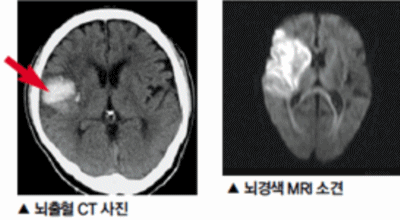

막힌 혈관으로도 혈액이 공급되긴 하나 혈관이 막혀있어 혈액을 보내긴 하나 제대로 흐르지 못하고 혈액이 쌓이고 축적되어 물풍선에 물이 꽉 차서 터지듯 뇌혈관이 터지는 경우가 일어날 수 있는데 이를 뇌출혈 이라고 해요. 물론 외상으로 인한 뇌출혈도 있지만 이처럼 뇌경색으로 인해 혈관이 막혀 터지는 경우도 있어요.